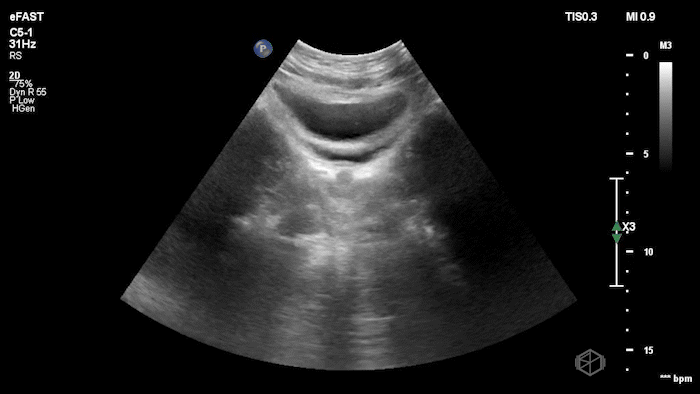

FAST/FAFF, Non-Obstetric Gynecologic Yash Chavda, DO, MBA 11/15/25 FAST/FAFF, Non-Obstetric Gynecologic Yash Chavda, DO, MBA 11/15/25

A woman with abdominal distention and a woman with abdominal pain and CVA tenderness…